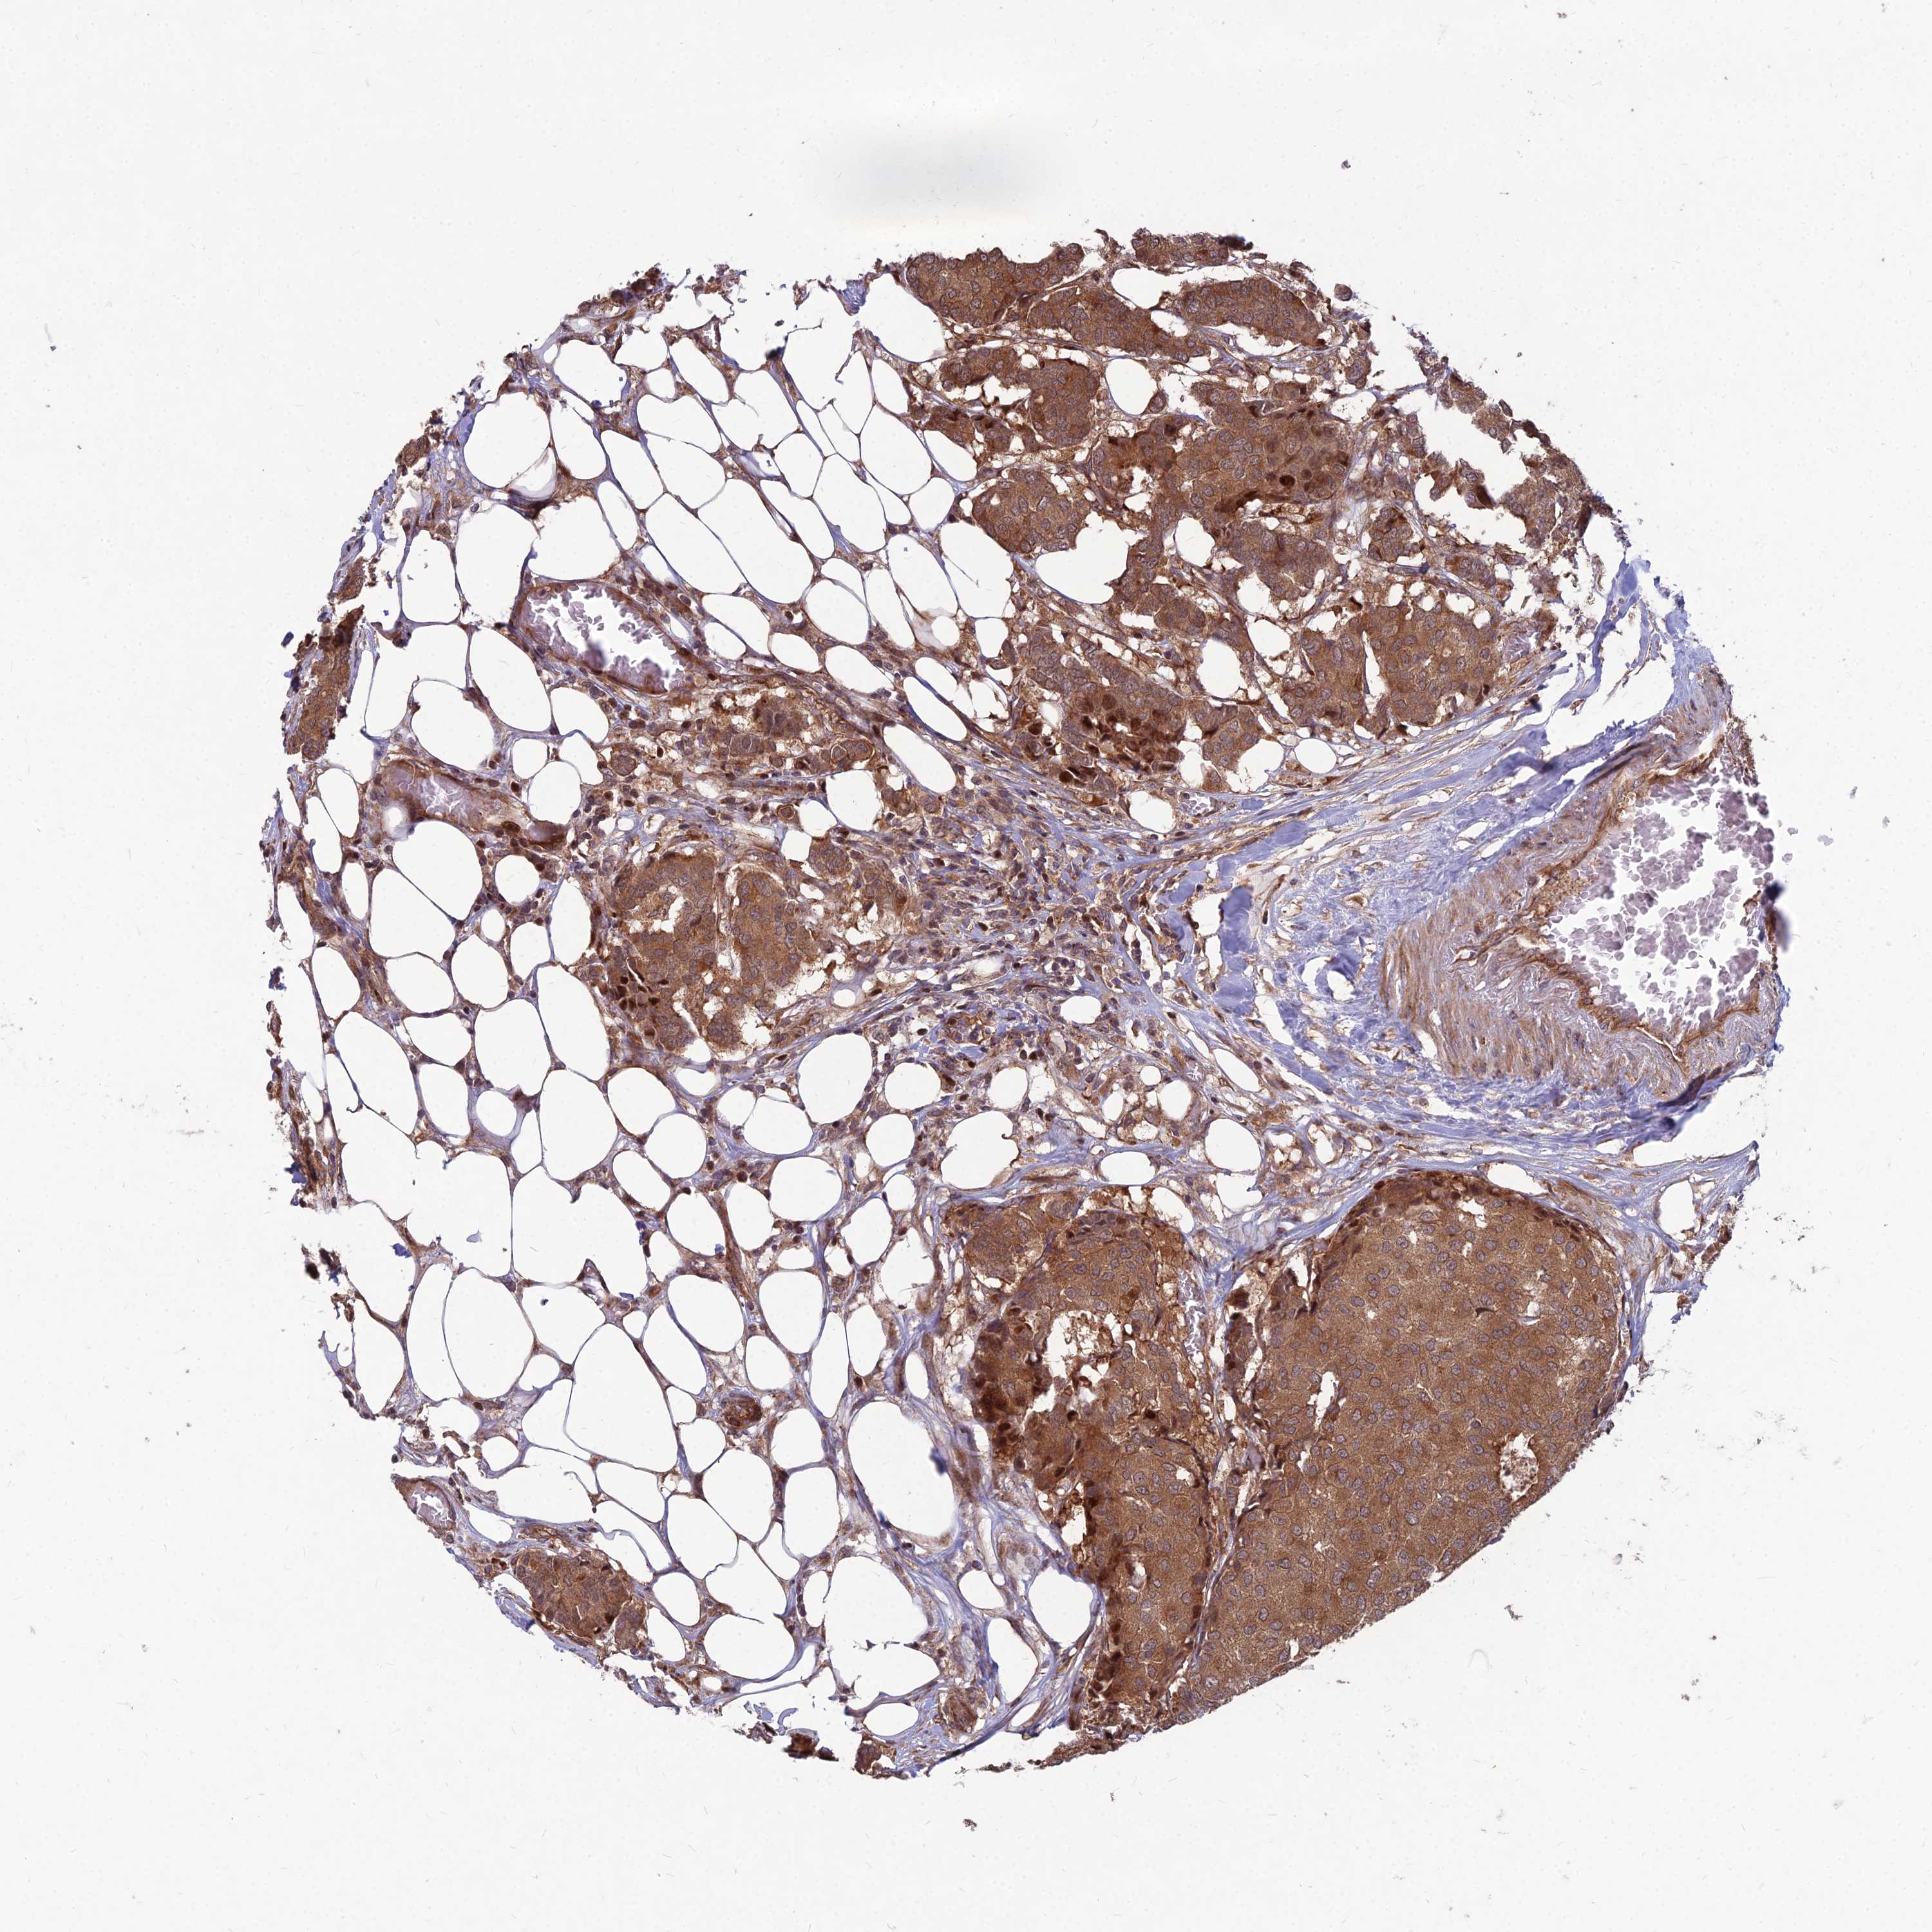

CANCER BREAST CANCER Show tissue menu

BRCA TCGA BRCA VALIDATION PROTEIN EXPRESSION